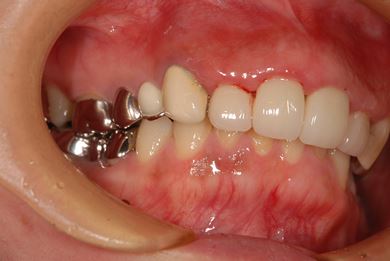

セラミックの症例写真 SHINBI

| 性別/年齢 | 女性 / 41歳 | ||||||||||||||||||||||||||||||||

| 主訴 | 歯が欠けたので、セラミック治療をお願いしたい。 | ||||||||||||||||||||||||||||||||

| 治療方針 | セラミック治療にて、審美的回復を行う。 | ||||||||||||||||||||||||||||||||

| 治療内容 | エンプレスオールセラミッククラウン4本(オールセラミック用土台4本) | ||||||||||||||||||||||||||||||||

| 総治療費 | 408,000円 | ||||||||||||||||||||||||||||||||

| 治療期間 | 4ヶ月 |